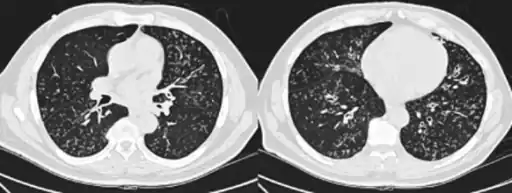

- High-resolution computed tomography scan of the thorax

- High resolution computed tomography (HRCT) images of the lower chest in a 16-year-old boy initially diagnosed with DPB (left), and 8 weeks later (right) after a 6-week course of treatment with erythromycin. The bilateral bronchiectasis and prominent centri-lobular nodules with a "tree-in-bud" pattern shows noticeable improvement.

The diagnosis of DPB requires analysis of the lungs and bronchiolar tissues, which can require a lung biopsy, or the more preferred high resolution computed tomography (HRCT) scan of the lungs.[7] The diagnostic criteria include severe inflammation in all layers of the respiratory bronchioles and lung tissue lesions that appear as nodules within the terminal and respiratory bronchioles in both lungs.[4] The nodules in DPB appear as opaque lumps when viewed on X-rays of the lung, and can cause airway obstruction, which is evaluated by a pulmonary function test, or PFT.[6] Lung X-rays can also reveal dilation of the bronchiolar passages, another sign of DPB. HRCT scans often show blockages of some bronchiolar passages with mucus, which is referred to as the "tree-in-bud" pattern.[7] Hypoxemia, another sign of breathing difficulty, is revealed by measuring the oxygen and carbon dioxide content of the blood, using a blood test called arterial blood gas. Other findings observed with DPB include the proliferation of lymphocytes (white blood cells that fight infection), neutrophils, and foamy histiocytes (tissue macrophages) in the lung lining. Bacteria such as H. influenzae and P. aeruginosa are also detectable, with the latter becoming more prominent as the disease progresses.[4][5] The white blood, bacterial and other cellular content of the blood can be measured by taking a complete blood count (CBC). Elevated levels of IgG and IgA (classes of immunoglobulins) may be seen, as well as the presence of rheumatoid factor (an indicator of autoimmunity). Hemagglutination, a clumping of red blood cells in response to the presence of antibodies in the blood, may also occur. Neutrophils, beta-defensins, leukotrienes, and chemokines can also be detected in bronchoalveolar lavage fluid injected then removed from the bronchiolar airways of individuals with DPB, for evaluation.[4][9]